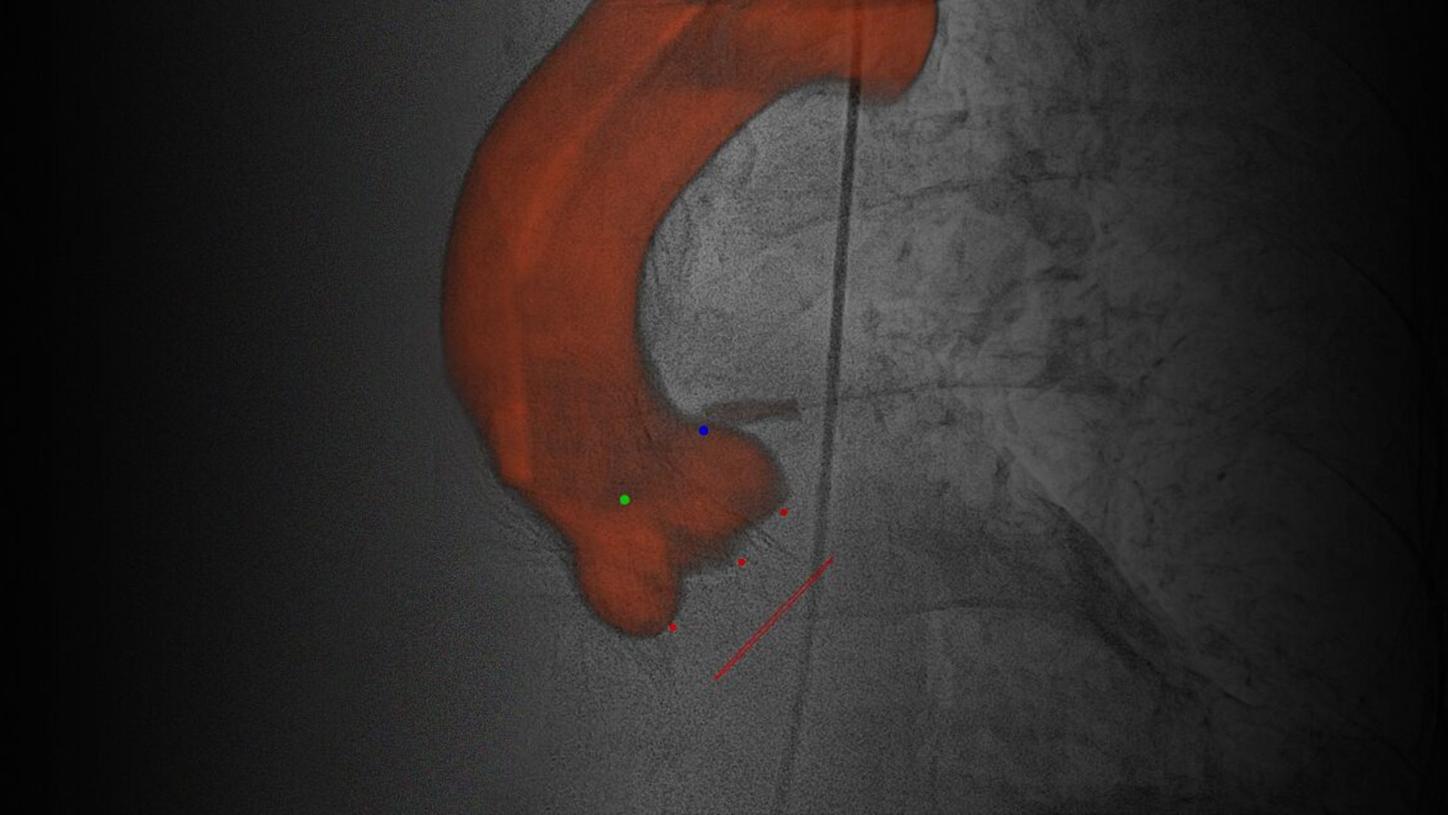

Material-specific imaging with Structure Scout

Structure Scout enables improved device visibility supporting ALARA dose due to material-specific optimization of imaging parameters.

With new devices and new materials appearing all the time, image-guided therapy is facing new challenges. Structure Scout adjusts the X-ray spectrum to material-specific acquisition parameters and optimizes visibility of materials, devices, vessels, and background structures independent of procedure or material type with our embedded structure-sensitive algorithm.

Precise system movements

Precision is key to improve the workflow in complex procedures. The reuse of vessel maps for DSA and 3D Roadmap even after C-arm and table movements speeds up the intervention and reduces dose and use of contrast media. ARTIS icono supports this with a (re)positioning accuracy of better than 0.5 mm.